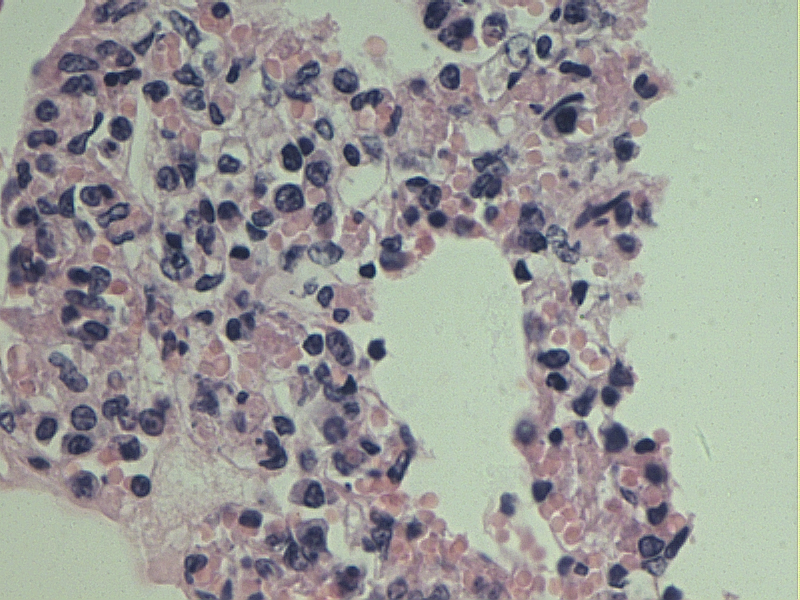

间质性肺炎

支气管周围大量炎性细胞浸润

肺泡隔增厚